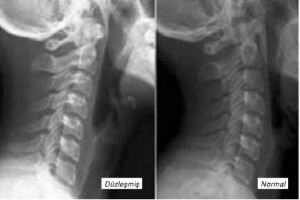

Boyun düzleşmesi neden olur. İnsan vücudundaki omurgaların belli bir duruşu ve şekli vardır bu duruş ve şekil zamanla belirli nedenlerden dolayı farklılaşarak bazı rahatsızlıklara sebep olabilir. Boyun düzleşmesinin çeşitli nedenleri vardır. Boyun düzleşmesi şiddetli ağrıya ve tedavi edilmediğinde tehlikeli sorunlara neden olabilen bir hastalıktır. Boyun düzleşmesi neden olur.

Boyun düzleşmesinin temel sebeplerinden biri uzun zaman hareket etmeden öne doğru eğik biçimde oturmaktır. çalışma hayatında edinilen yanlış duruş bozuklukları uzun süre aşağı doğru bakarak okuma ve çalışma alışkanlığı bankacılar gazeteciler yazarlar muhasebeciler gibi bilgisayarın sık kullanıldığı meslekler müzisyenlik ressamlık yazarlık seramik heykeltıraşlık fabrikaların montaj bandında çalışma vb. Boyun düzleşmesi şekli c ye benzeyen omurganın aşırı yüklenme aşırı stres ve stres gibi nedenlerden dolayı omurganın i şeklini almasıdır. Bu ağrılar streste çok artar.

Bu nedenler arasında disk hastalığı boyun fıtığı veya dejenerasyonu içinden geçen sinirlerin hastalıkları trafik kazası kemik ve eklem hastalıkları neden olabileceği gibi kötü pozisyonda oturarak kitap okumak veya bilgisayar kullanmak neden olabilir. En önemli nedeni servikal omurganın dikkat halindeymiş gibi sürekli dik durmasına neden olan anormal bir eğridir. Boyun düzleşmesinin en yaygın nedeni uyanıkken veya uyurken uzun süre bozuk bir duruşta kalmaktır. Ama çoğu vaka egzersiz ve yaşam tarzı değişiklikleri ile iyileşmektedir.